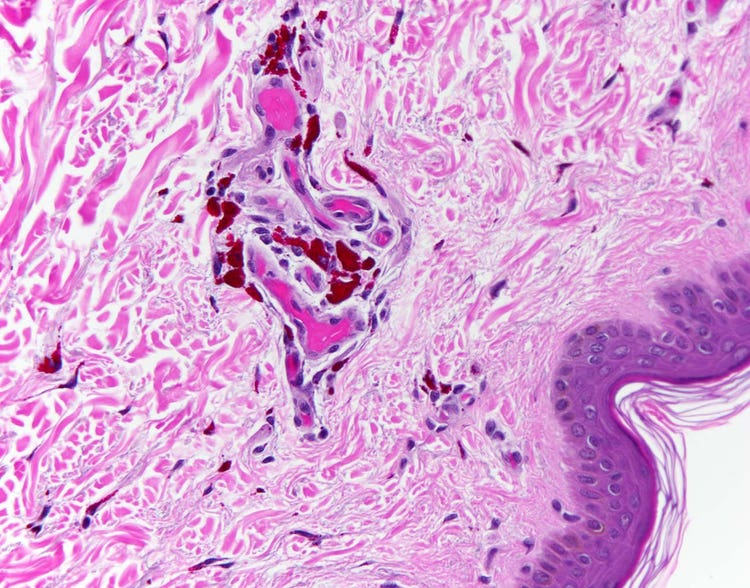

Pentachrom-Färbung eines Blutgefäßes unter dem Mikroskop

Schnitt durch eine normale menschliche Arterie mit Movat Pentachrom-Färbung, bei der fünf verschiedene Farbstoffe verwendet werden, um verschiedene Aspekte der subzellulären Anatomie hervorzuheben. So erscheinen beispielsweise die elastischen Fasern in der Arterienwand, die dem Blutgefäß Festigkeit und Elastizität verleihen, bei einer Pentachrom-Färbung schwarz. Aufgenommen mit einem Olympus BX43 Mikroskop und einer DP26 Kamera. Bildquelle: Dr. Marianne Hamel.